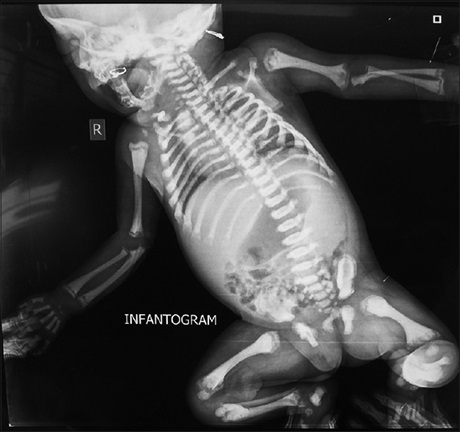

Multisystemic Anomalies in Conjoined Twins: The Role of Imaging in Management

Dr. Mohammed Kabir Saleh, Austine Abebe Osawe, Idris Sule Kazaure, Mohammad Abba Suwaid, Abdulkadir Musa Tabari, Kabiru Isyaku, Isma’il Anas (Author)

86-89